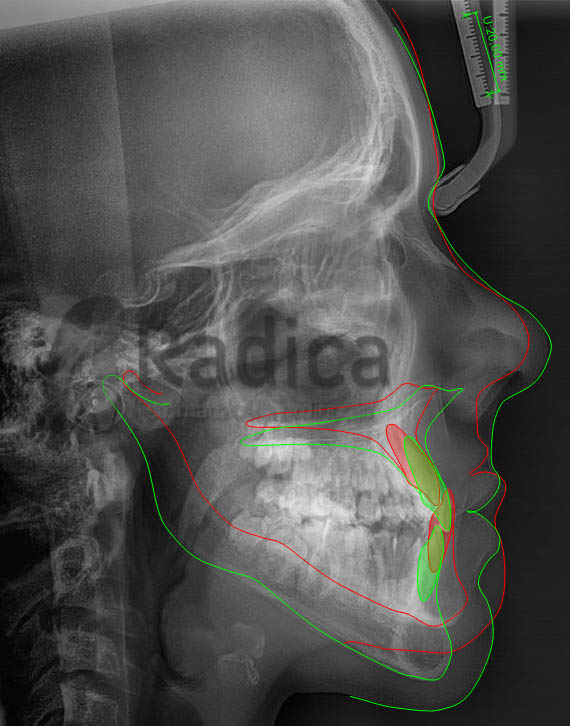

Na superpoziciji lateralne slike glave prije i poslije terapije se vide promjene u rastu.

Stanje prije terapije je označeno crvenom bojom, a zelenom je označeno stanje poslije terapije